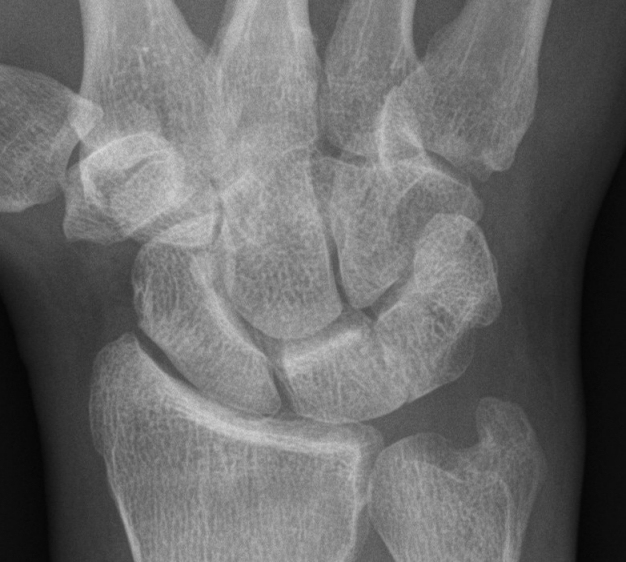

A 35-year-old right-hand dominant white male launderer presented in our policlinic with right-sided wrist pain since 7 months after he had fallen on the same hand. He described an ulno-dorsal intermittent stabbing pain on twisting his hand, particularly when bearing loads. Physical examination revealed tenderness located in the luno-triquetral joint. No swelling or ache in other locations of the right hand could be found. On examination, the left wrist was completely asymptomatic and there was no pathologic “shuck” and “shear” test between the lunate and the triquetrum [10]. The range of motion of the right wrist was 40-0-30 degrees for extension and flexion whereas the left wrist showed no restricted functionality. Plain radiographs showed a right-sided coalition of the lunate and triquetrum (Figure 1 [Fig. 1]), as well as an incomplete fibro-cartilaginous coalition type I on the left side (not shown). Radial and ulnar clenched fist views of both wrists showed no anomaly.

Figure 1: Plain radiograph of the right wrist giving the impression of a luno-triquetral coalition type II of Minaar’s Classification